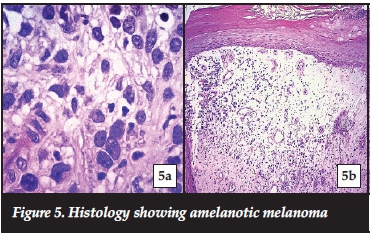

Once the case was discussed with an oncologist, informed consent was obtained from the patient to perform a partial amputation of the hallux. The hallux was amputated at the level of the mid-shaft of the proximal phalanx, allowing for at least a 15mm clear margin from the tumour edge (Figures 4a and 4b). The histology report once again confirmed the amelanotic melanoma, stage lib (Figure 5), with 20 mm clear margins. The patient was referred to the oncology unit for further treatment as required.

The authors wish to acknowledge Dr B Wium for providing the histological pictures used in this manuscript.